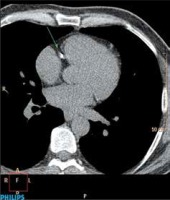

Cardiac computed tomography examinations were performed without intravenous administration of the contrast agent. Proprietary protocols included in the software of these devices were used to conduct heart examinations. Patients were tested after resting, without the use of medications to slow down the heart rate.

On a Phillips Brilliance Workstation and using HeartBeat CS v. 5.5 software the amount of calcification in coronary arteries was measured. Calculation of this parameter was carried out in a semi-automatic manner. In the first part of the calculations, the software automatically marked a calcification. Coronary calcification was defined as an area of the size of 3 adjacent voxels that were located along the course of the coronary artery and their density was greater than 130 Hounsfield units. Then, after identifying coronary arteries, the study evaluator confirmed that calcifications marked by the software were indeed in those arteries. Then, final results, the Calcium Score according to the Agatston scale (CS), the volume of calcifications in coronary arteries (CV) and the mass of these calcifications (CM) were calculated automatically by the software of the devices (Figure 1).